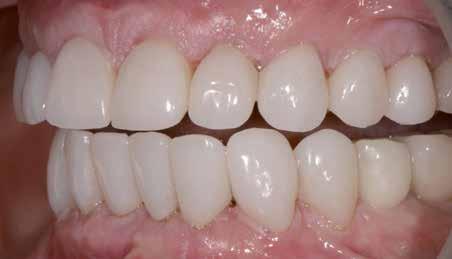

Hölgy páciensem az első konzultáció során tipikus kórtörténetet vázolt fel: Gyermekkora óta szeretett volna fogszabályozó készüléket, hiszen mindig is zavarta a class 2-es eltérésnél tipikusan jellemző nagy overjet (1-3. képek), és természetesen az ezáltal kifelé álló felső metszőfogai, részben a felső metszők protrúziója, részben pedig a disztálisan elhelyezkedő mandibula miatt. Annak ellenére, hogy több fogszabályozó szakorvosnál is járt az évek során, de mivel saggitális eltérése és az alsó metszőfogak torlódása miatt négy kisőrlőfog extrakcióját, illetve emellett sokszor állcsont műtétet is javasoltak neki, nem vágott bele a kezelésbe (4-5. képek).

A konzultáció során arról is beszéltünk – ahogy az ilyenkor lenni szokott –, sohasem szeretett igazán mosolyogni, de a Pitts Protokolloknak köszönhetően az arc- és mosolyesztétikai céloknak megfelelően kerül megvalósításra az okklúziós korrekció. Az okklúziós kezelési célok az alábbiak voltak: a felső és alsó fogív nivellálása és tágítása, az alsó fogsor/ mandibula mezializálása, valamint a harapás megemelése által a mélyharapás rendezése.

Az esztétikai kezelési céloknál a Pitts elvek szerint a legfontosabb fogak a felső, középső metszők, a cél ezeknek a tökéletes pozícióba állítása. A legfontosabb, hogy a felső, középső metszők labiális felszíne merőleges legyen a Frankfurti Horizontálisra, vagyis természetes fejtartásnál (Natural Head Position) párhuzamos legyen a vertikális síkkal (6. kép) Ehhez az ideális pozícióhoz képest minél protrudáltabbak a felső metszők, annál laposabb, szemből nézve kevésbé ívesebb lesz a mosolyvonal, másrészt optikailag a metszők

hossza is rövidül, azaz a Vertical Incisor Display (Metszőfog láthatóság) csökken. A miniesztétikai, vagyis a mosolyesztétikai eredmény szempontjából egyik jelenség sem kívánatos. A mikroesztétika (a fog- és ínyesztétika) is szorosan hozzátartozik az esztétikai paraméterekhez, ennek tökéletesítése is minden esetben a célok közé tartozik fogkontúrálással vagy esztétikai fogászati felépítéssel, továbbá interproximális redukcióval és szükség esetén lézeres ínykontúrálással (7. kép).

A fogkontúrálás és az interproximális redukció alkalmazásával a mikroesztétikai részletek tökéletesítése is megtörtént (11. kép) A kezelés mindössze 16 hónapig tartott, megtörtént a rágófunkció helyreállítása, és az esztétikai végeredmény sokéves várakozás után valóban fordulópontot jelentett páciensünk életében (12-14. képek).